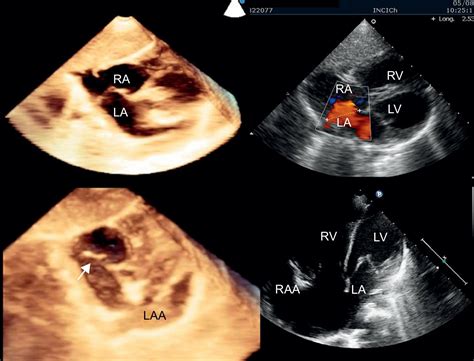

• Echocardiogram: This ultrasound test provides detailed images of the heart's structure and function, allowing doctors to visualize the aneurysm.

• Transesophageal Echocardiogram (TEE): This more invasive procedure involves inserting a probe down the throat to get a clearer view of the heart's structures.